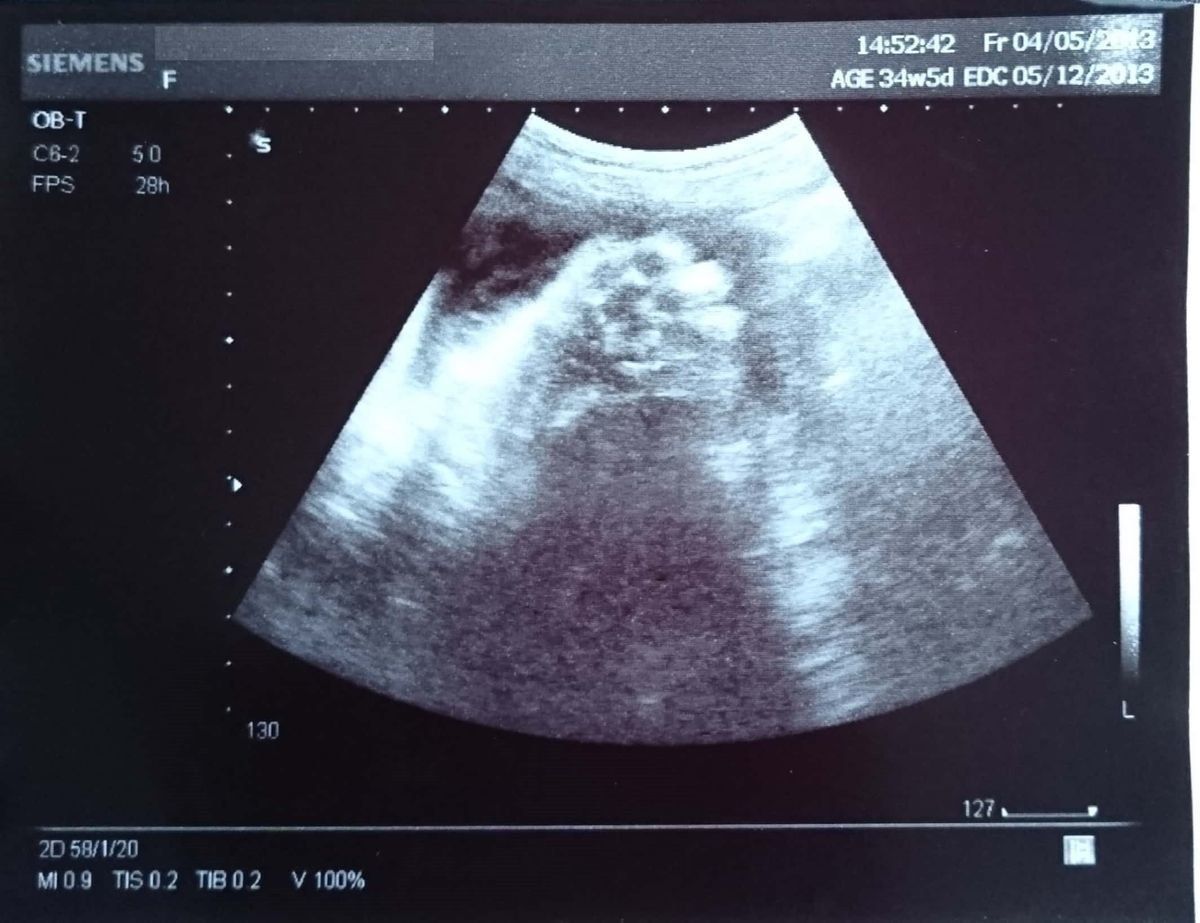

妊娠34週のエコー写真 大きくなってきたのでパーツのエコー写真ばかりに

見えているのは、手か足です。この頃になると、ラストスパートとばかりにおなかが大きくなり、下に引っ張られるような重さを感じるように。通りがかりの女性に「予定日は来週くらい?」と聞かれるほど。歩くのも徐々につらくなってきました。また、ときどき生理痛に似た鈍い痛みを感じるようになりました。妊娠37週頃にいわゆる「おしるし」のようなおりものがあり、予定より2週間早い出産となりました。